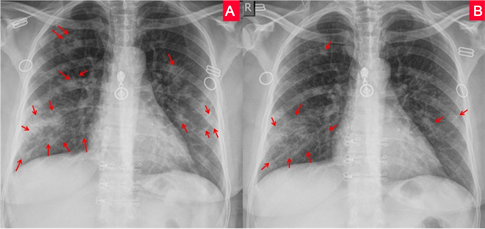

This study was conducted based on monitoring the lung changes using serial of images up to 4 radiographs per patient according to Figures 2-6. Their radiological finding and monitoring characteristics are summarized in Table 2.

Figure 2. Series of chest x-rays in a 48-year-old man with COVID-19. (A): PA chest x-ray obtained on day 1 illness shows negative radiological finding with score zero; (B): PA chest x-ray obtained on day 5 illness shows bilateral mid and lower zone ground-glass opacity with central and peripheral lower zone consolidation with score 5; (C): PA chest x-ray obtained on day 9 illness shows multifocal bilateral nodular and patchy consolidation at upper, mid, and lower zones with score 5; (D): PA chest x-ray obtained on day 17 illness shows the dissipative stage with regression of the consolidations into the peripheral ground glass and reticular opacity seen in the mid and lower zones bilaterally with score 3.

Figure 3. Two chest x-rays in a 54-year-old woman with COVID-19. (A): PA chest x-ray obtained on day 3illness shows bilateral peripheral lower zone ground glass opacity and consolidation with score 4; (B): PA chest x-ray obtained on day 12 illness shows remaining few bilateral middle and lower zone ground-glass opacity which are seen at peripheral regions with regression course and score 4.

Figure 4. Series of chest x-rays in a 68-year-old man with COVID-19. (A): AP chest x-ray obtained on day 4 illness shows diffuse bilateral ground-glass opacity with multifocal central and peripheral nodular patchy consolidation with score 6; (B): AP chest x-ray obtained on day 6 illness shows progression course and diffuse bilateral ground-glass opacity with multifocal central and peripheral nodular patchy consolidation with score 6; (C): AP chest x-ray obtained on day 10illness shows the same degree of lung involvement; bilateral diffuse patch consolidation affecting both lung fields with score 6; (D): AP chest x-ray obtained on day 13 illness shows remaining bilateral diffuse patch consolidation affecting both lung fields, more to the right.

Figure 5. Two chest x-rays in a 40-year-old woman with COVID-19. (A): PA chest x-ray obtained on day 7 illness shows right upper, middle, and lower zone ground-glass opacity with peripheral lower zone consolidation, left middle and lower zone ground-glass opacity and small nodular patches with score 5; (B): PA chest x-ray obtained on day 13 illness shows right upper, middle, and lower zone ground-glass opacity with peripheral lower zone consolidation. Also, mild improvement is noted with score 3.

Figure 6. Series of chest x-rays in a 33-year-old man with COVID-19. (A): PA chest x-ray obtained on day 4 illness shows bilateral ground-glass opacity with nodular patches at mid and lower zones, central in a location with score 4; (B): PA chest x-ray obtained on day 8 illness shows remaining bilateral ground-glass opacity with nodular patches at mid and lower zones, medial and peripheral in a location with score 4 too; (C): PA chest x-ray obtained on day 13 illness shows bilateral ground-glass opacity at mid and lower zones, central and peripheral in location with lesser extent compared with A and B with score 5; (D): PA chest x-ray obtained on illness day 21 shows good improvement; the dissipative stage of mild bilateral trabecular reticular opacity pattern with minimal left peripheral ground-glass opacity with score 1.